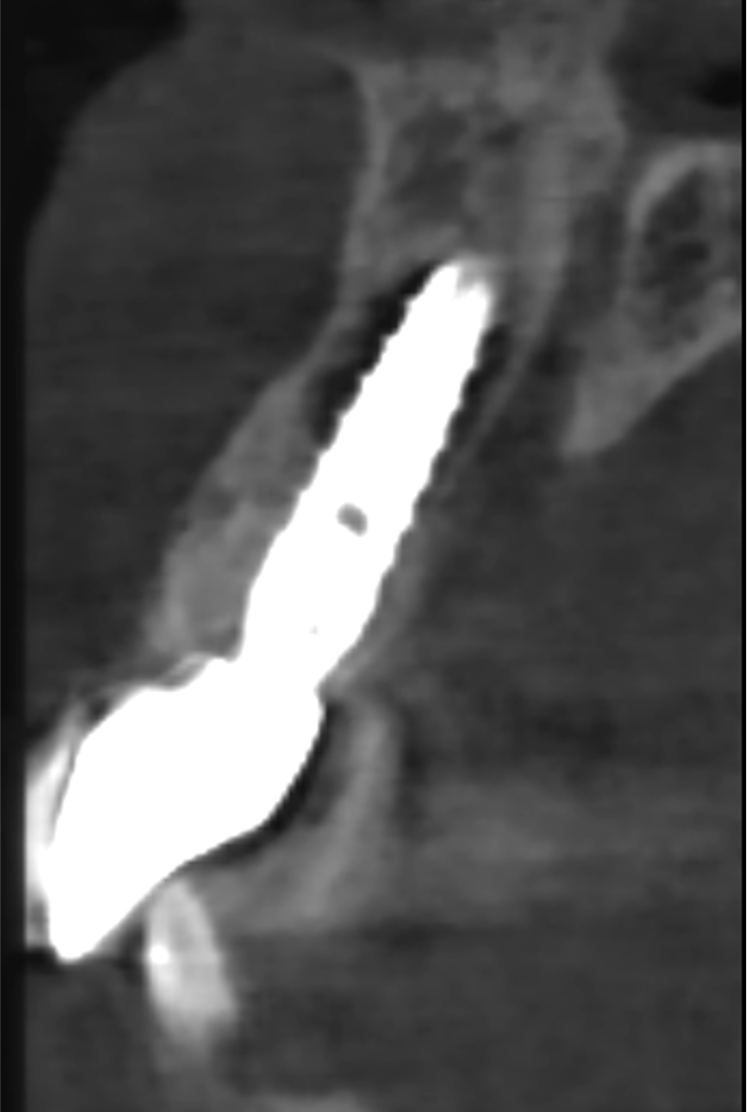

After 6 months, an optical impression was taken (Carestream 3600) and a final screw-retained crown made of zirconia. From the CT cone beam 1 year after the extraction, bone regeneration was evident right up to the anodized neck of Prama implant.

X-ray one-year control